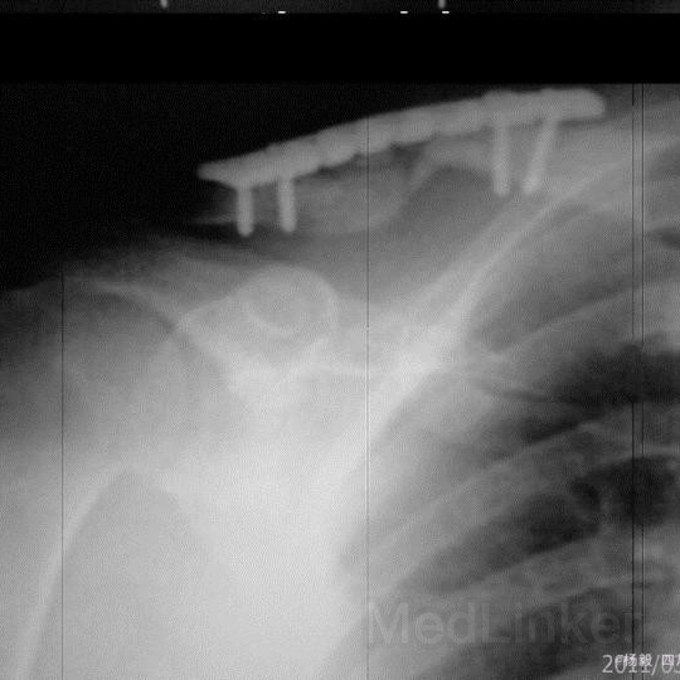

右锁骨粉粹性骨折内固定术后4月。因外伤致右锁骨粉粹性骨折,已行手术内固定4月,锁骨带固定近两月。术后四十天,锁骨内侧伤口红肿破溃,有肉芽形成,伤口约0.5cm大小,能探及钢板,一直门诊换药,现伤口未愈。请教诸位:目前采取积极态度清创后植骨内固定,还是保守治疗,要不要继续外固定?请各位发表高见。